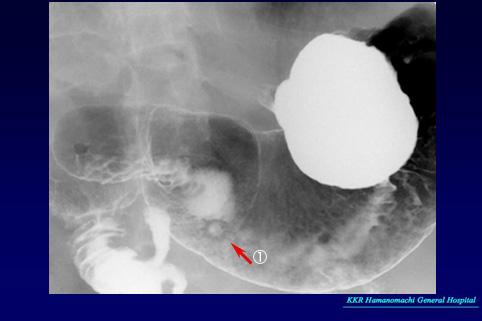

疾病(病理主体)的分类恶性上皮肿瘤/其他

部位(按器官分)胃(部位)/前庭

检查方法X线

肿瘤的肉眼分类0型(表在型)/IIa型(IIa+IIc)

肿瘤最大直径15~19

肿瘤的深度sm

多发性肿瘤(同一器官)有(同时性)